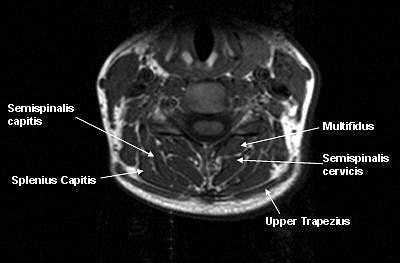

The patient population for this cross-sectional study consisted of 20 WAD subjects and 32 healthy controls in the U.S. and Australia. At the U.S. facility, images were collected on a 1.5-tesla scanner (Horizon LX, GE Healthcare, Chalfont St. Giles, U.K.) using a conventional spin-echo sequence. In Australia, a 1.5-tesla scanner also was used (Sonata, Siemens Medical Solutions, Malvern, PA). The protocol included T1-weighted axial conventional spin-echo pulse sequences to obtain tissue contrast of fat to muscle.

For the image analysis, regions of interest (ROI) were drawn over each bilateral cervical extensor muscle on the axial T1-weighted images at each vertebral segment (C0-C7). The authors also tested the reliability of MRI in this setting.

According to the results, MRI showed a higher level of fat within all extensor muscles in the WAD group. Also in this group, the multifidus muscle showed significantly higher fat content at each level. The largest amounts of intramuscular fat were pinpointed in the rectus capitis posterior minor and major, and the deep cervical multifidi muscles, the authors stated.

"The higher levels of fatty infiltrate in the suboccipital ... and multifidus muscles ... could lead to the contention that there was a greater injury with consequent change in the muscles at these segments. It is possible that those with upper cervical injuries may be more prone to chronicity," the group explained, adding that some of the symptoms associated with WAD -- headache, unsteadiness -- are associated with upper cervical structures.